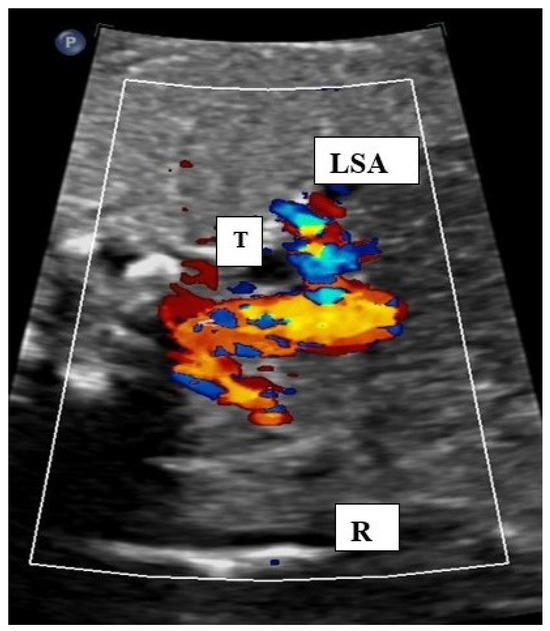

4.1. AAA Diagnostics of AAA and Accuracy Rate